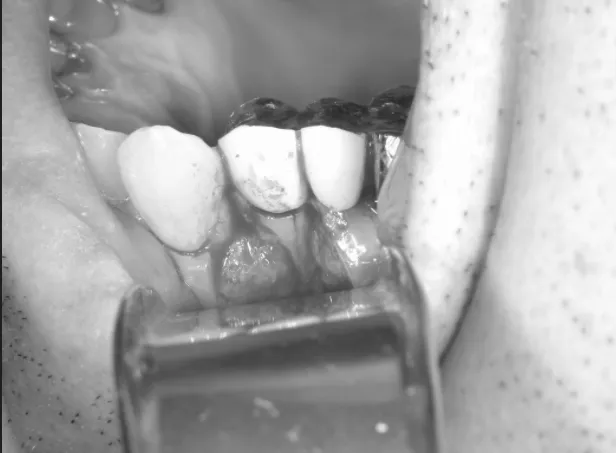

今回お見せしている写真では歯茎を切開し開いて炎症の場所を直視している状態です。

拡大図

拡大してみると、歯を支えている骨が溶けている部分に一致した歯の亀裂があります。

ここの亀裂に細菌が侵入し、周りに炎症が起こることで骨が吸収し歯茎が腫れてしまっています。

この亀裂はCT撮影では写ってこない亀裂であったため、初めは根尖性歯周炎による歯茎の腫れと診断され歯根端切除を行う予定でした。

しかし、亀裂が手術時に発見され、今回のように縦断破折を認めてしまうと治療方針は大きく変わり抜歯が治療の最善策になります。